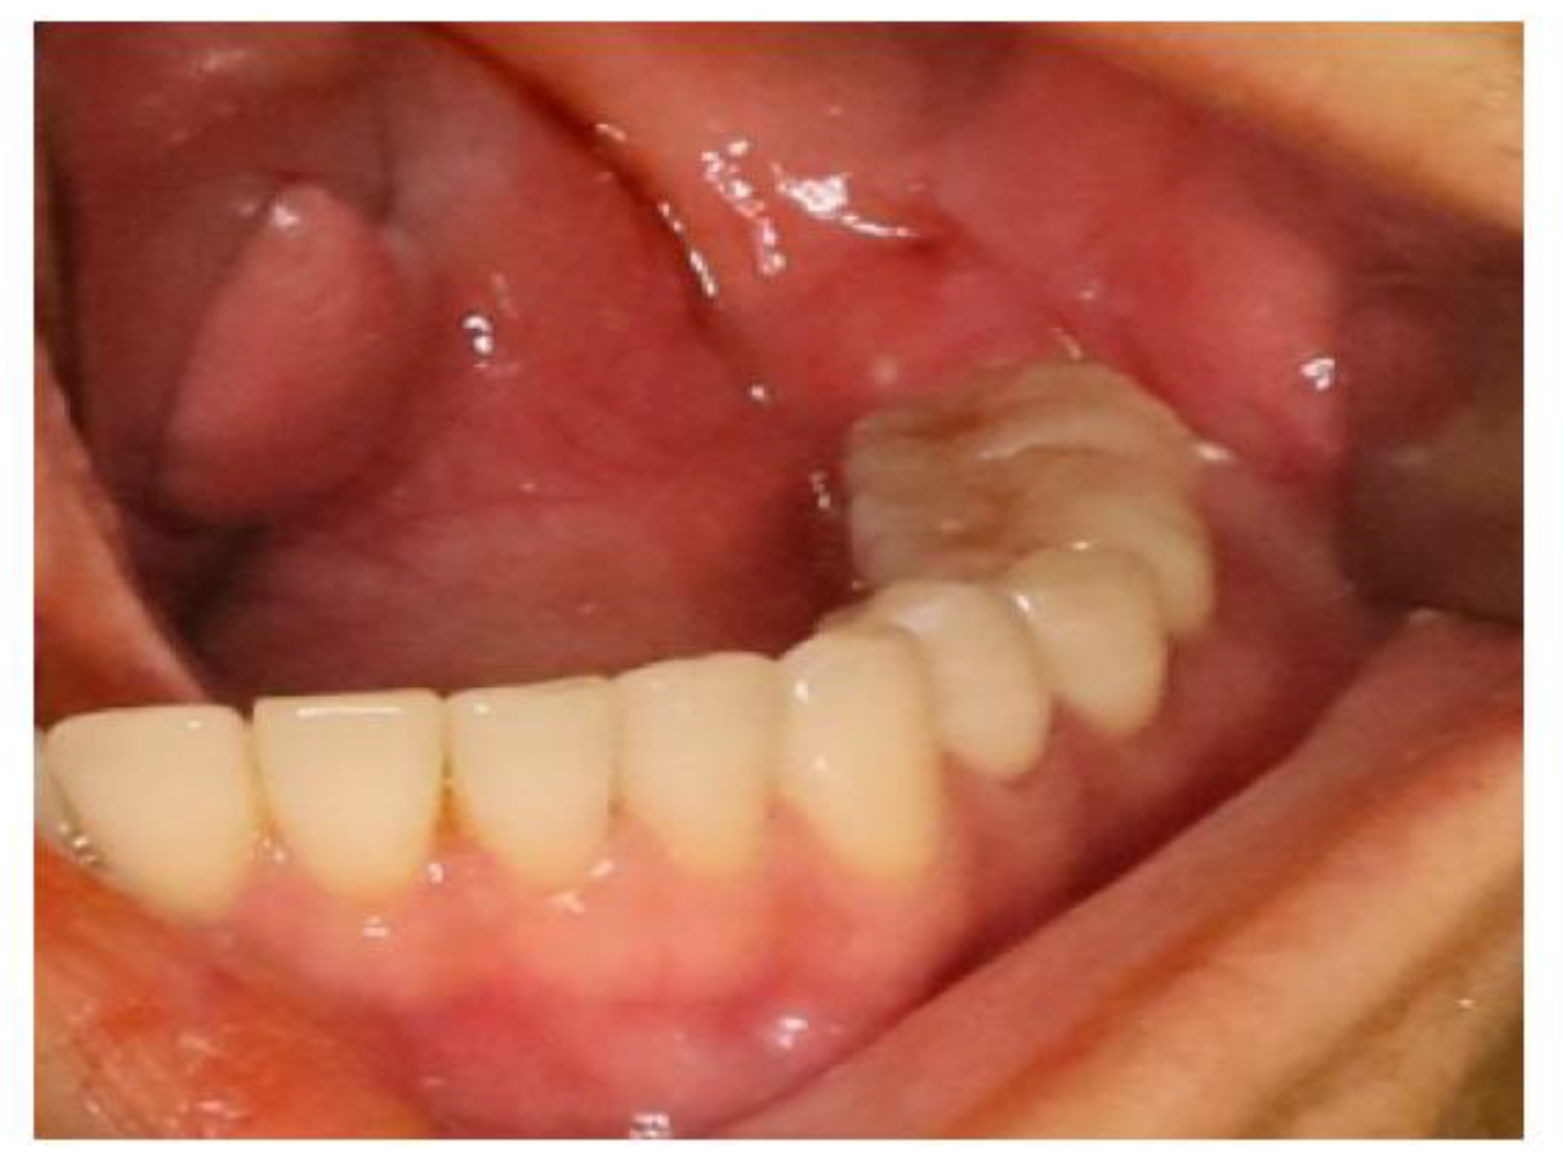

2.2. Case 2